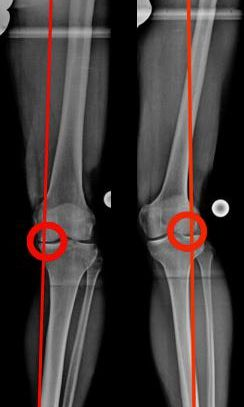

Die Röntgenaufnahme des gesamten Beines, im Stehen, ist unabdingbar. Ihre Analyse zeigt, über das Ausmaß der Fehlstellung, wie die Lastverteilung im Knie stattfindet und inwiefern die Knorpelschicht ausgedünnt ist. Dabei werden spezifische Winkel ausgemessen (Bild 1c) anhand welcher das weitere Vorgehen geplant werden kann.

Beispiel einer aufklappenden Osteotomie, kniegelenksnah, am Schienbein bei O-Beinfehlstellung. Die MA wurde zentriert, da noch keine Schädigung des Gelenkes vorlag (Bild 2).